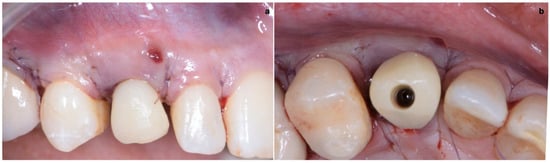

2.3. Provisional Restoration

As shown in Figure 13, the maturation of soft tissue at 1 month (a), 3 months (b) and 6 months (c) after surgery was evident. The peri-implant soft tissues were conditioned with the provisional crown until the shape and position for the mucosal scallop to resemble the gingival margin of the adjacent corresponding tooth and the progressive growth of peri-implant papillae were obtained [19]. In this phase, the patient was called every 2 weeks for us to check the provisional restoration. At the end of the conditioning phase, it was possible to place the definitive, screw-retained restoration (Figure 14a–c).

Figure 13. Maturation of soft tissue at 1 month (a), 3 months (b) and 6 months (c) after surgery.

Figure 14. (ac) Conclusion of the conditioning phase.